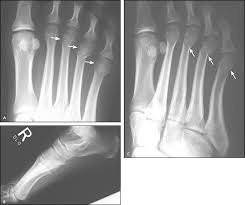

After a visit to a doctor, a complete evaluation is done to evaluate the injury. The majority of them need medical imaging in order to be diagnosed properly. Of the two most common pieces of diagnostic equipment for metatarsal fractures, they are:

- X-rays: They are the first line for determining whether or not there is a fracture, where and how it is located.

- MRI or CT Scan: These may be employed occasionally if stress fractures are suspected or to scan for soft tissue damage surrounding the bone.